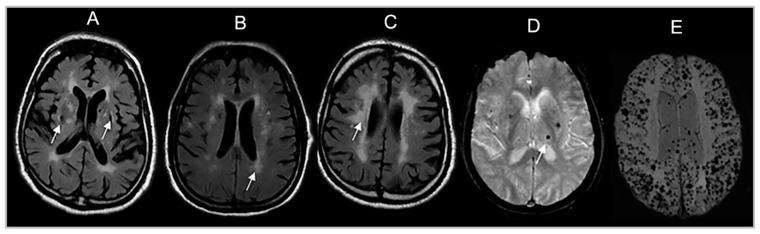

Perivascular spaces (PVS) visible on brain MRI signal cerebral small vessel disease (CSVD). The coexistence of PVS with other CSVD manifestations likely increases the risk of adverse neurological outcomes. We related PVS to other CSVD manifestations and brain volumes that are markers of vascular brain injury and neurodegeneration. Framingham Heart Study (FHS) participants with CSVD ratings on brain MRI were included. PVS were rated in the basal ganglia (BG) and centrum semiovale (CSO) into grades I-IV and a category reflecting high burden in single or mixed CSO-BG regions. We related PVS to covert brain infarcts (CBI), white matter hyperintensities (WMH), cerebral microbleeds (CMB), total brain, hippocampal, and cortical gray matter volumes using adjusted multivariable regression analyses. In 2454 participants (mean age 54 ± 12 years), we observed that higher PVS burden in both BG and CSO was related to CMB in lobar and deep brain regions and increased WMH. Greater CSO PVS burden was associated with decreased total cortical gray volumes. PVS are associated with ischemic markers of CSVD and neurodegeneration markers. Further studies should elucidate the causality between PVS and other CSVD manifestations.

脑磁共振成像(MRI)上可见的血管周围间隙(PVS)提示脑小血管病(CSVD)。PVS与其他CSVD表现共存可能会增加不良神经结局的风险。我们将PVS与其他CSVD表现以及作为血管性脑损伤和神经退行性变标志物的脑容量进行了关联研究。纳入了在脑MRI上有CSVD评分的弗雷明汉心脏研究(FHS)参与者。对基底节(BG)和半卵圆中心(CSO)的PVS进行分级,分为I-IV级以及反映单个或混合CSO-BG区域高负荷的类别。我们使用校正后的多变量回归分析将PVS与隐匿性脑梗死(CBI)、白质高信号(WMH)、脑微出血(CMB)、全脑、海马和皮质灰质体积进行关联。在2454名参与者(平均年龄54±12岁)中,我们观察到BG和CSO中较高的PVS负荷与脑叶和深部脑区的CMB以及增加的WMH相关。CSO中更大的PVS负荷与总皮质灰质体积减少相关。PVS与CSVD的缺血标志物和神经退行性变标志物相关。进一步的研究应阐明PVS与其他CSVD表现之间的因果关系。